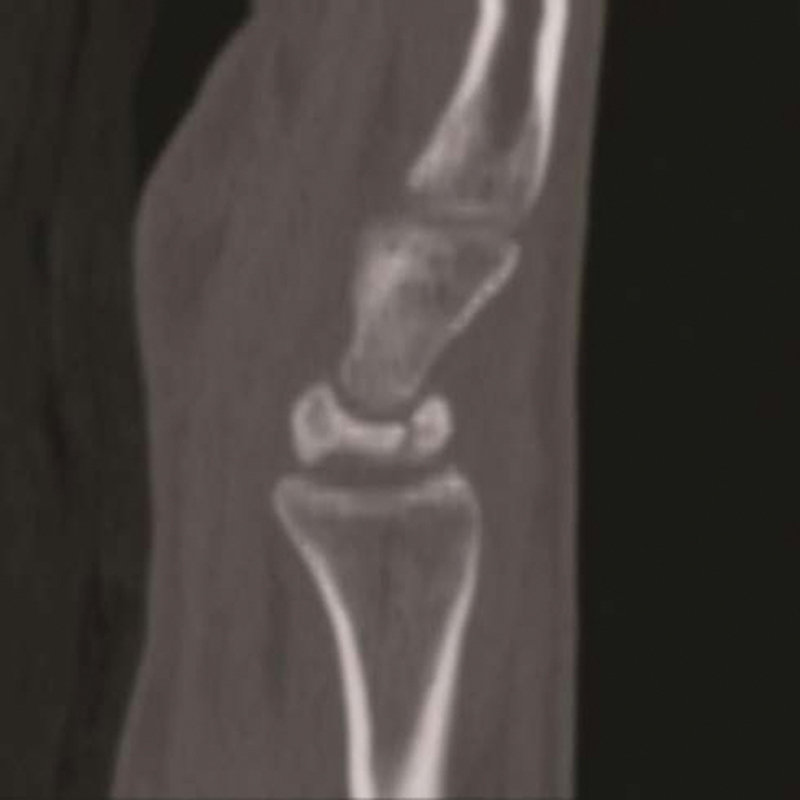

Fig. 2.

In transitional Kienböck's central cavitation precedes subsequent proximal subchondral collapse.